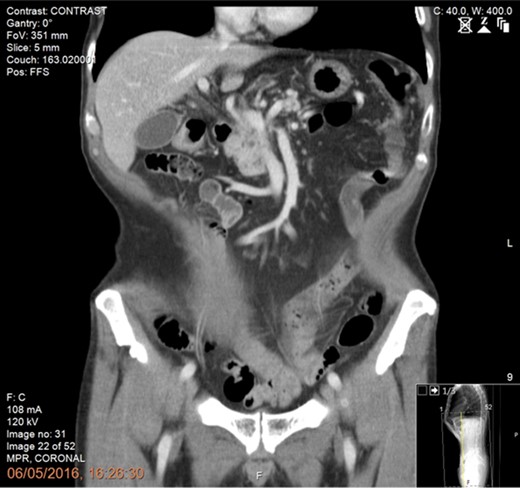

A 61-year-old man diagnosed in January 2016 with a T4N1M0 BRPC in the uncinate process of the pancreas with venous involvement and complete occlusion of the superior mesenteric vein (SMV) and no evidence of metastatic disease (Fig. 1).

CT scan of the abdomen and pelvis (portal phase) demonstrating a borderline resectable pancreatic tumour at the uncinate process with involvement and complete occlusion of the superior mesenteric vein (SMV) and abutment of the superior mesenteric artery.